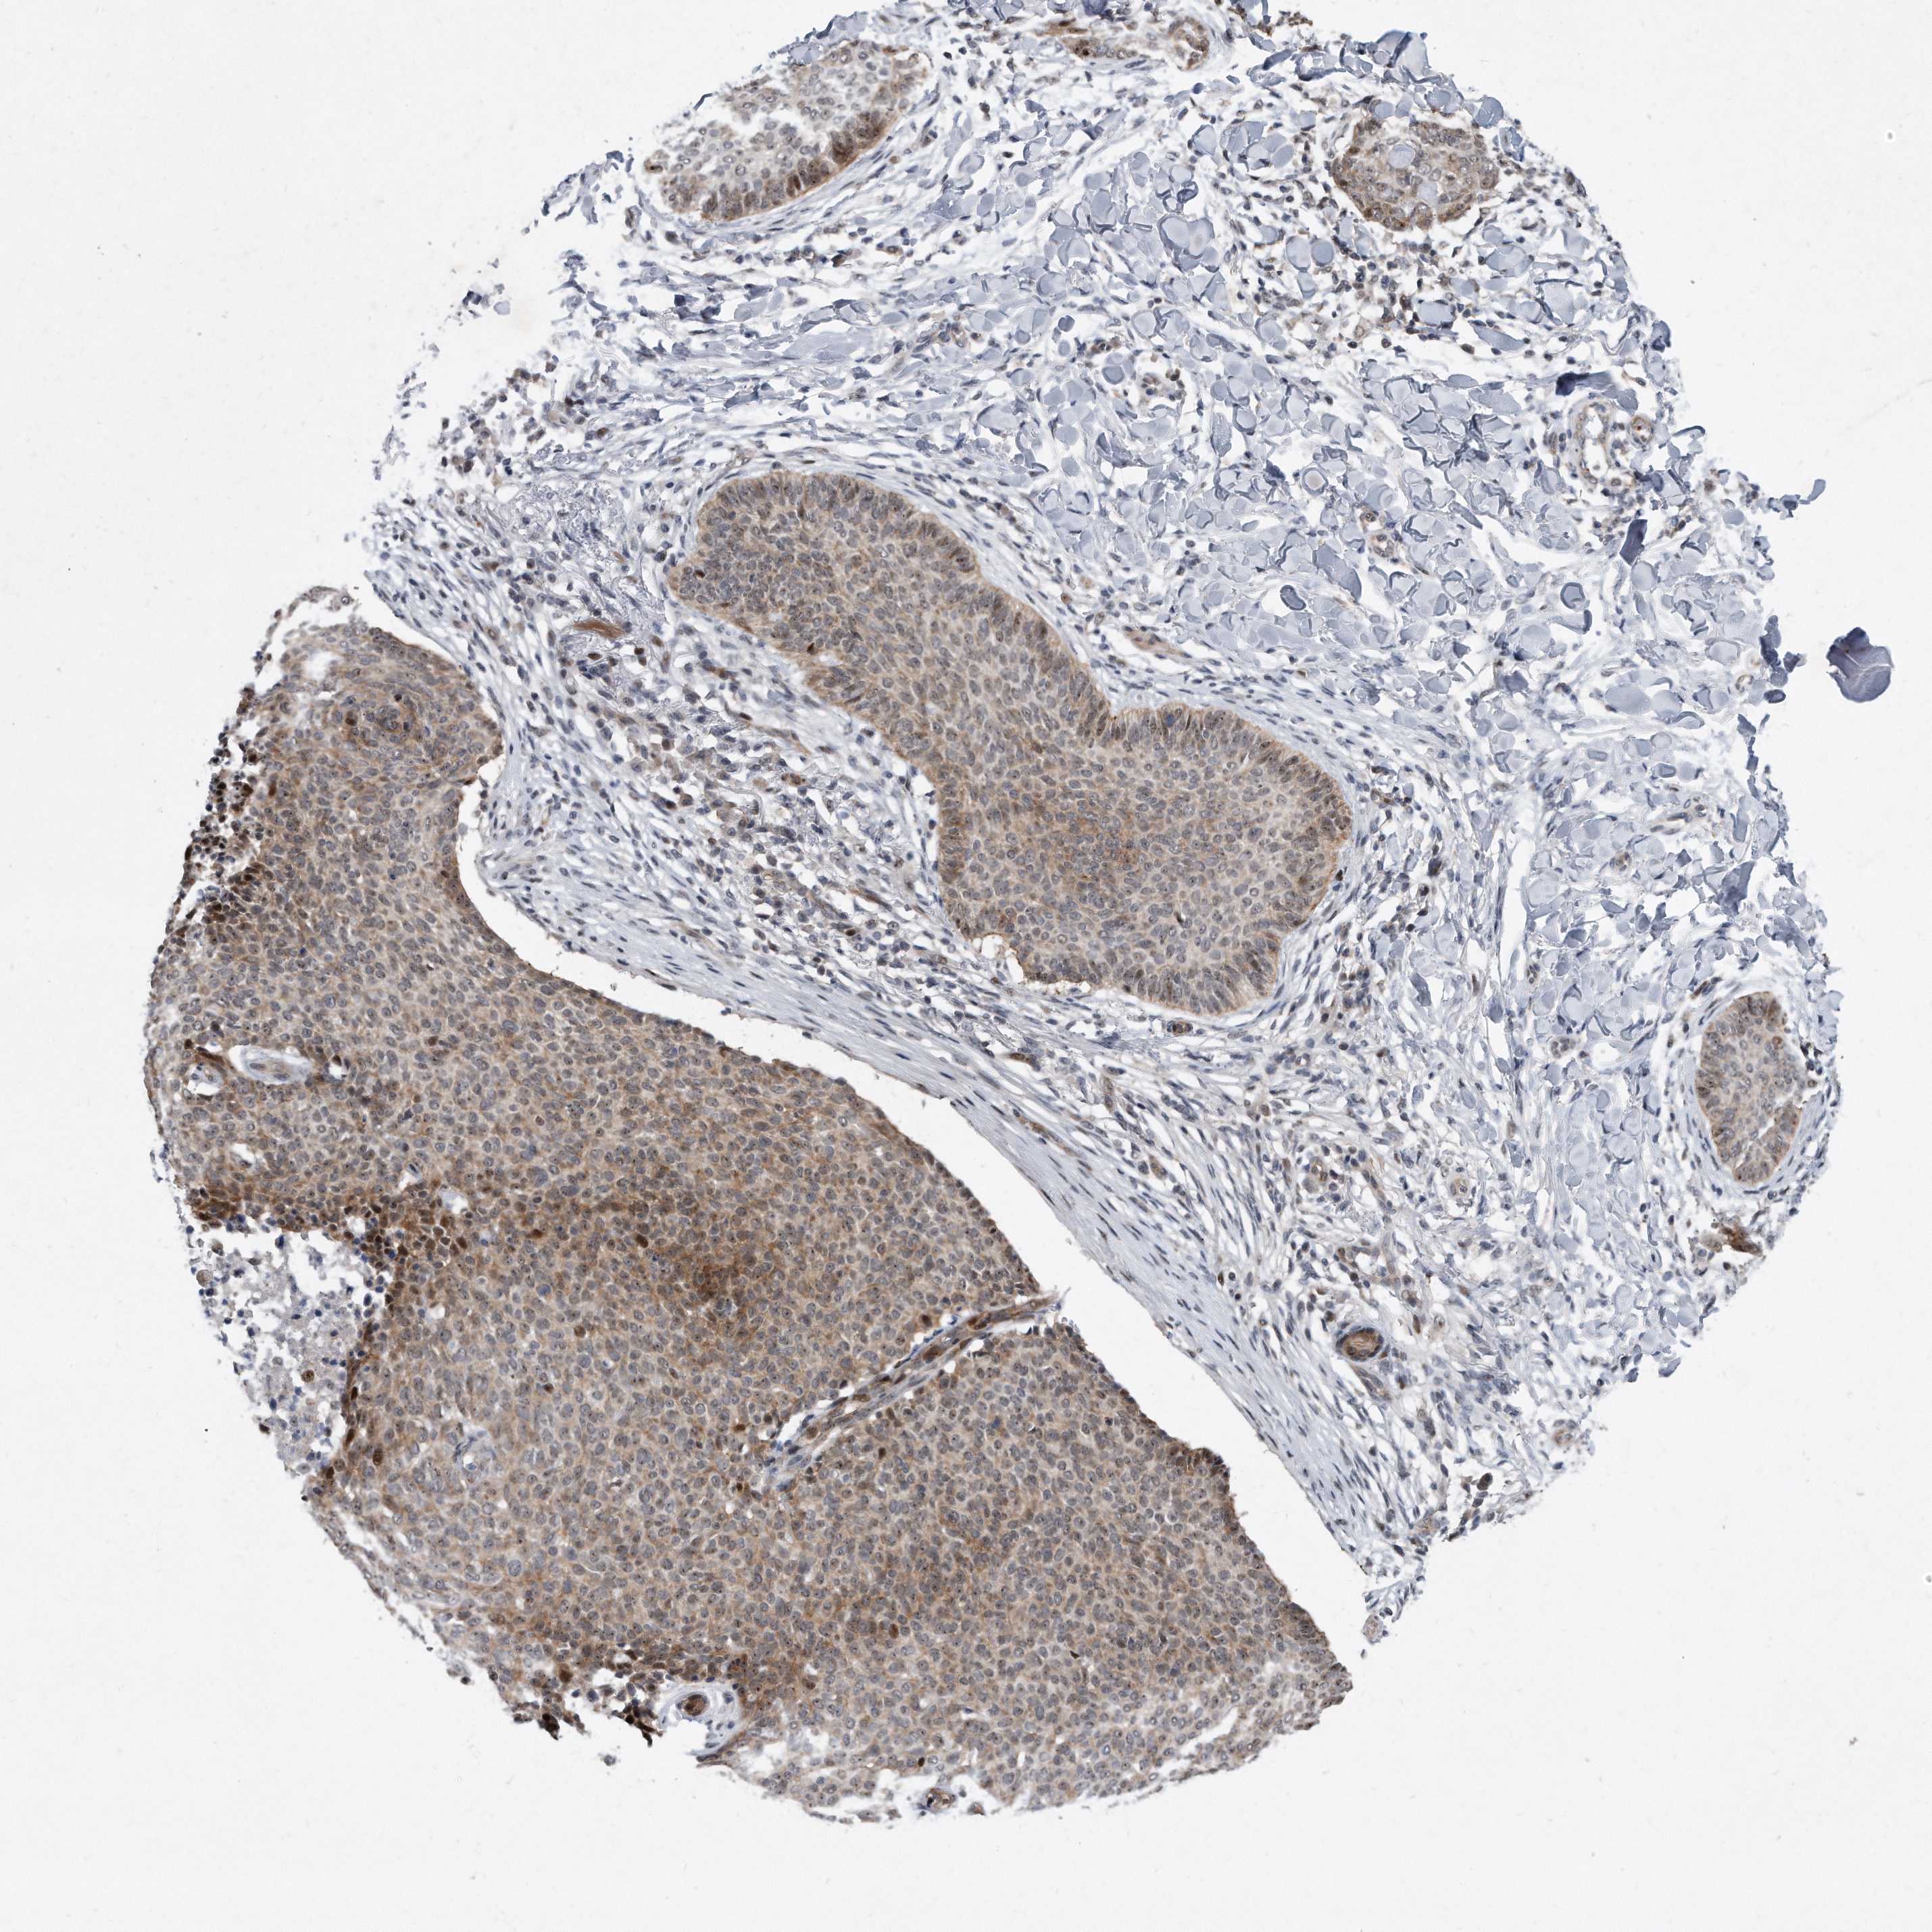

SKIN CANCER - Protein expressioni

A mouse-over function shows sample information and annotation data. Click on an image to view it in a full screen mode. Samples can be filtered based on level of antibody staining by selecting one or several of the following categories: high, medium, low and not detected. The assay and annotation is described here.

Each image is clickable and will lead to virtual microscopy that enables deeper exploration of all samples and also displays staining intensity scores, fraction scores and subcellular localization as well as patient and tissue information for each sample.

Antibody HPA029888

Basal cell carcinoma